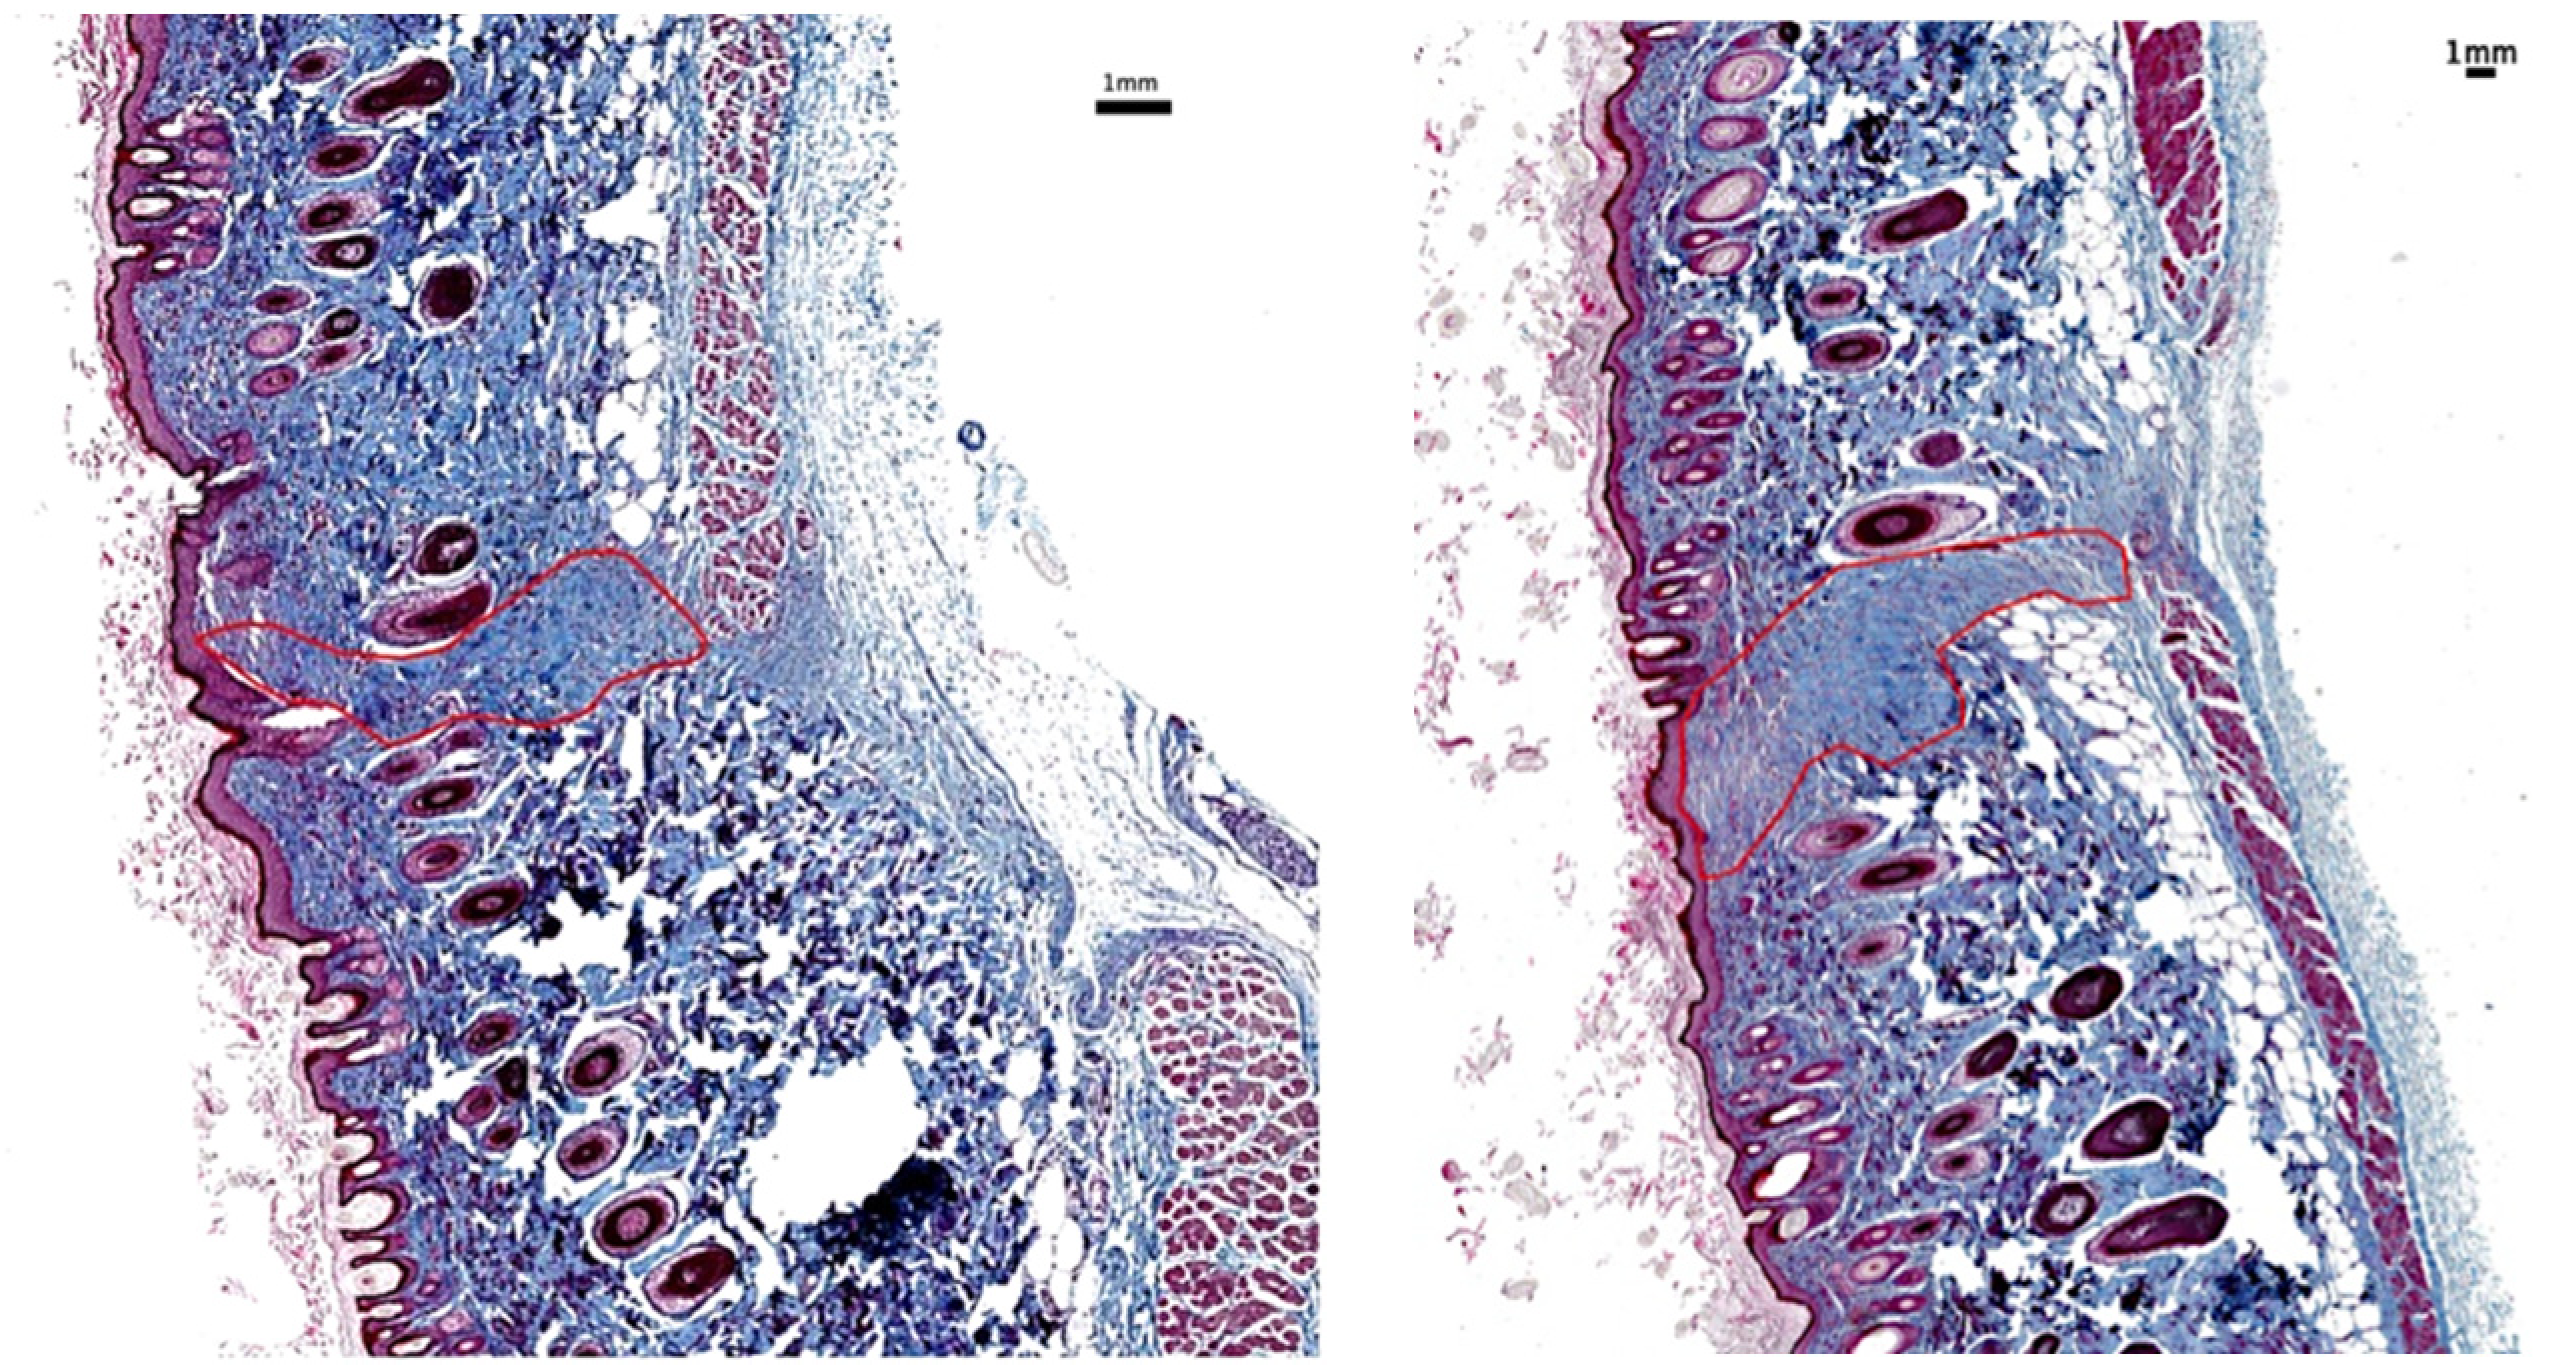

Morphometric wound analysis reveals site-specific differences in healing for the two types of incisions. While not quantified, in tissue samples collected 1 day after surgical incision, subcutaneous blood staining was frequently observed in incisions made with the SB and less frequently with the EB (Figure 3). Monitoring blood staining was not part of the experimental plan. Within 3 days after skin incisions, the majority of wounds produced by SB did not achieve closure (Figure 4). In contrast, approximately 90% of incisions made by EB exhibited adherence in this same period. The results show that the wound treated with SB did not close completely on the third day; however, the one treated with EB did. By day 7, all wounds achieved closure. After 2 months, all incisions were completely healed, and the dorsal skin softness and elasticity were qualitatively judged to be normal.

Figure 4.

Wound H&E histology: morphological changes, closure, and re-epithelialization 3 days post-injury: Left: incision by EB; right: incision by SB; bottom: full representative sample with incision by EB (left) and SB (right).

Figure 8 and Figure 9 are representative images of wound histology at 16 days and 2 months post-surgery, respectively. The difference in the amount of scar produced by the EB versus the SB is apparent. In addition, the scar area width is narrower along the incision made with the EB in comparison with that corresponding to the SB.

Figure 8.

Scar histology 16 days post-surgery: Histological sample stained with trichrome at 16 days post-surgery showing less scarring in region of EB skin incision (left) than SB skin incision (right).